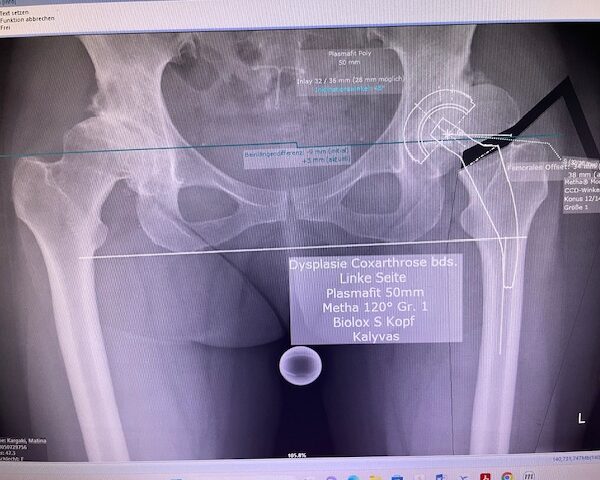

Ο προεγχειρητικός ψηφιακός σχεδιασμός ήταν ιδιαίτερα μεθοδικός και συγκεκριμένος. Η ακτινογραφία λεκάνης της ασθενούς εισήχθη σε ειδικό λογισμικό στον υπολογιστή, το οποίο επέτρεψε τον ακριβή προγραμματισμό της καινούριας θέσης της άρθρωσης.

Μέσω του ψηφιακού αυτού σχεδιασμού, υπολογίστηκε με ακρίβεια το μέγεθος και ο τύπος των προθέσεων, η γωνία του κώνου, καθώς και η σωστή ανατομική τοποθέτηση των μοσχευμάτων. ώστε να επιτευχθεί τέλειος ισοσκελισμός των κάτω άκρων και να αποφευχθεί οποιαδήποτε διαφορά μήκους μετεγχειρητικά!!!

Πρόκειται για ένα εξαιρετικά σημαντικό στάδιο, καθώς εξασφαλίζει τη μέγιστη δυνατή ακρίβεια, ταχύτητα και αποτελεσματικότητα κατά τη διάρκεια της επέμβασης. Επιπλέον, συμβάλλει στην άριστη λειτουργικότητα του ισχίου καθώς και να επιτευχθεί τέλειος ισοσκελισμός των κάτω άκρων και να αποφευχθεί οποιαδήποτε διαφορά μήκους μετεγχειρητικά!!!

Ο προεγχειρητικός ψηφιακός σχεδιασμός αποτελεί πάντα πλήρως εξατομικευμένο πλάνο, προσαρμοσμένο στα ανατομικά χαρακτηριστικά και τις ανάγκες του κάθε ασθενούς, και είναι καθοριστικός για την επιτυχία της επέμβασης !!!